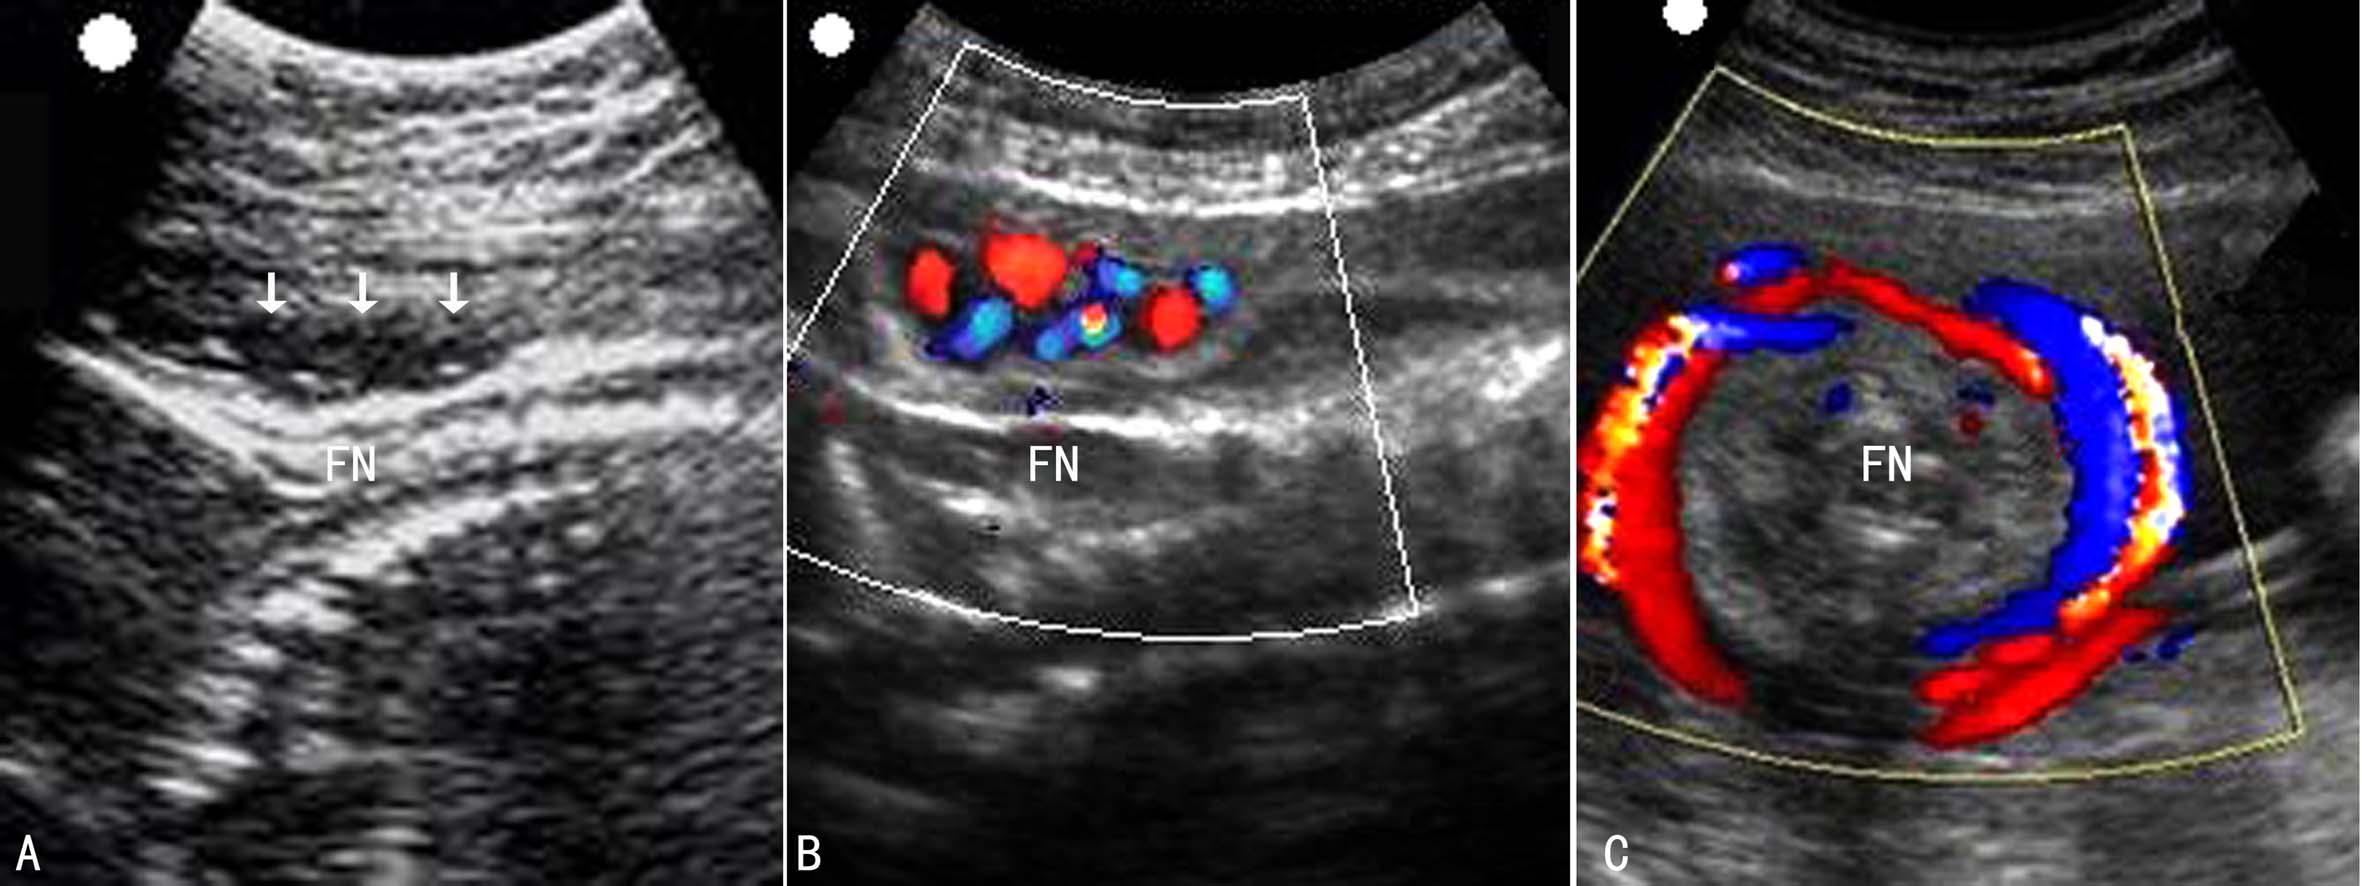

2.超声显像 超声显像检查纵向扫查胎儿颈部,正常时胎儿枕部和颈部脊柱表面的皮肤呈平滑的曲度。如果发现颈项部皮肤出现“U”形或“W”形压迹,诊断脐带绕颈多无疑问,一般认为“U”形压迹多由一圈脐带绕颈形成,而“W”形压迹可由两圈以上脐带绕颈形成;适当降低仪器增益、仔细观察有时还可以在压迹的表面显示脐带回声(图1A)。但缺少脐带回声的直接显示多不影响对脐带绕颈的诊断。

3.超声多普勒血流显像 在超声显像的引导下启动彩色多普勒血流显像可以在压迹表面直接显示脐带的血流图像(图1B)。显示两色、三条血管时至少有绕颈一圈,如果显示两色、能分辨至少四条以上血管即提示绕颈多于一圈;横切面可显示环绕颈部的脐带血流(图1C)。绕颈的脐带内血流速度较快、阻力增高(图2),其他部位的脐带内血流多无异常改变。如果发现非绕颈部位脐动脉血流异常时,尤其是S/D大于3.0时,应及时提示临床积极处理,避免严重的胎儿宫内窘迫发生。

图1脐带绕颈超声检查显示